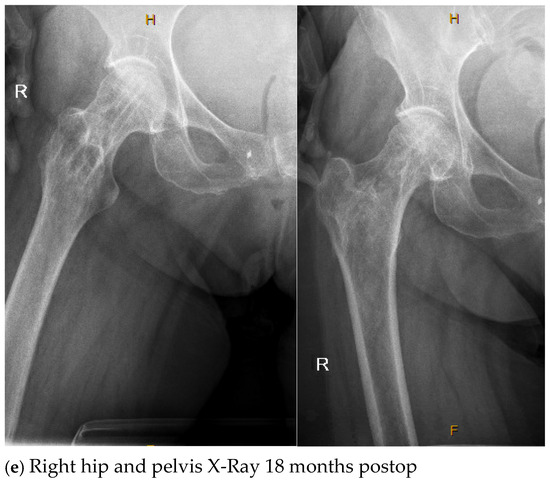

| 4. | 75 | F | Y | N | 20 | N | N | 17 | Right thigh and gluteal abscess with infected right femoral neck hardware and osteomyelitis |

| 4. | N | N | 14 | 4 | Y, clinical and lab | 107 | Negative |